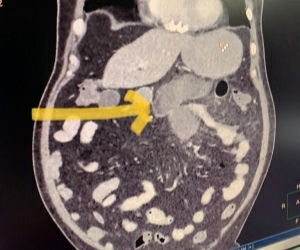

а§∞а§Ња§Ја•На§Яа•На§∞а•Аа§ѓ а§∞а§Ња§Ь৲ৌ৮а•А а§Ха•З а§Па§Х а§Еа§Єа•Н৙১ৌа§≤ а§Ѓа•За§В а§Ѓа•На§ѓа•Ва§Ха•Ла§∞а•На§Ѓа§ња§Ха•Ла§Єа§ња§Є (а§ђа•На§≤а•Иа§Х а§Ђа§Ва§Ча§Є) а§Ха•А а§Па§Х ৮а§И а§Ьа§Яа§ња§≤১ৌ а§Ха§Њ ৙১ৌ а§Ъа§≤а§Њ а§єа•И, а§Ьа§ња§Єа§Ѓа•За§В а§Ђа§Ва§Ча§≤ а§Єа§Ва§Ха•На§∞а§Ѓа§£ ৮а•З ৶а•Л а§Ѓа§∞а•Аа§Ьа•Ла§В а§Ха•А ৮ড়а§Ъа§≤а•А а§Жа§В১ а§Ха•Л а§Єа§Ва§Ха•На§∞ুড়১ а§Ха§∞ ৶ড়ৃৌ а§єа•Иа•§ а§З৮ а§Ѓа§∞а•Аа§Ьа•Ла§В а§Ѓа•За§В а§Па§Х 56 ৵а§∞а•На§Ја•Аа§ѓ а§Ра§Єа§Њ ৵а•На§ѓа§Ха•Н১ড় а§≠а•А ৴ৌুড়а§≤ а§єа•И, а§Ьড়৪৮а•З а§Ха•Л৵ড়ৰ а§Ха•З а§Ха§Ња§∞а§£ а§Е৙৮а•А ৙১а•Н৮а•А ৪৺ড়১ ৙а§∞ড়৵ৌа§∞ а§Ха•З ১а•А৮ ৪৶৪а•На§ѓа•Ла§В а§Ха•Л а§Ца•Л ৶ড়ৃৌ а§єа•Иа•§

68 а§Єа§Ња§≤ а§Ха•З а§Е৮а•На§ѓ а§Ѓа§∞а•Аа§Ь а§Єа§Ѓа•З১ ৶а•Л৮а•Ла§В а§Ѓа§∞а•Аа§Ьа•Ла§В а§Ха§Њ а§За§≤а§Ња§Ь ৶ড়а§≤а•На§≤а•А а§Ха•З а§Єа§∞ а§Ча§Ва§Ча§Њ а§∞а§Ња§Ѓ а§Еа§Єа•Н৙১ৌа§≤ а§Ѓа•За§В а§Па§Х а§єа§Ђа•Н১а•З а§Єа•З а§Ьа•Нৃৌ৶ৌ а§Єа§Ѓа§ѓ а§Єа•З а§Ъа§≤ а§∞а§єа§Њ а§єа•Иа•§ а§Ча§Ва§Ча§Њ а§∞а§Ња§Ѓ а§Еа§Єа•Н৙১ৌа§≤ а§Ха•З а§Еа§Іа§ња§Ха§Ња§∞а§ња§ѓа•Ла§В ৮а•З а§Ха§єа§Њ, а§ѓа§є ৙৺а§≤а•А а§ђа§Ња§∞ ৶а•За§Ца§Њ а§Ча§ѓа§Њ а§єа•И а§Ха§њ а§ђа•На§≤а•Иа§Х а§Ђа§Ва§Ча§Є ৮а•З ৮ড়а§Ъа§≤а•А а§Жа§В১ а§Ха•Л а§Єа§Ва§Ха•На§∞ুড়১ а§Ха§∞ ৶ড়ৃৌ а§Фа§∞ а§ѓа§єа§Ња§В ১а§Х а§Ха§њ а§Йа§Єа§Ѓа•За§В а§Ыа•З৶ а§≠а•А а§Ха§∞ а§¶а§ња§ѓа§Ња•§

৶ড়а§≤а•На§≤а•А а§Ха•З а§∞৺৮а•З ৵ৌа§≤а•З а§Ха•Ба§Ѓа§Ња§∞ (а§Е৮а•Ба§∞а•Ла§І ৙а§∞ ৐৶а§≤а§Њ а§Ча§ѓа§Њ ৮ৌু) ৮а•З а§Е৙৮а•А ৙১а•Н৮а•А а§Ха•З а§Еа§В১ড়ু а§Єа§Ва§Єа•На§Ха§Ња§∞ а§Ха•А ৙а•На§∞а§Ха•На§∞а§ња§ѓа§Њ ৙а•Ва§∞а•А а§єа•А а§Ха•А ৕а•А, а§Ха§њ а§Й৮а•На§єа•За§В ৙а•За§Я а§Ѓа•За§В ৶а§∞а•Н৶ а§єа•Л৮ৌ ৴а•Ба§∞а•В а§єа•Л а§Ча§ѓа§Ња•§ а§Й৮а•На§єа•За§В а§Е৙৮а•А ৙১а•Н৮а•А а§Ха•З ৪ৌ৕ а§єа•А а§Ха•Ла§∞а•Л৮ৌ а§Єа§Ва§Ха•На§∞а§Ѓа§£ а§єа•Л а§Ча§ѓа§Њ а§•а§Ња•§ а§єа§Ња§≤а§Ња§Ва§Ха§њ ৴а•Ба§∞а•Ба§Ж১ а§Ѓа•За§В а§Ха•Ба§Ѓа§Ња§∞ а§Ха•Л а§Ха•Ла§∞а•Л৮ৌ а§Ха•З а§єа§≤а•На§Ха•З а§≤а§Ха•На§Ја§£ а§єа•А ৕а•За•§

а§Єа§∞ а§Ча§Ва§Ча§Њ а§∞а§Ња§Ѓ а§Еа§Єа•Н৙১ৌа§≤ а§Ха•З а§Еа§Іа§ња§Ха§Ња§∞а§ња§ѓа•Ла§В ৮а•З а§Ха§єа§Њ а§Ха§њ ৴а•Ба§∞а•В а§Ѓа•За§В ১а•Л а§∞а•Ла§Ча•А а§Ха•З ৙а•За§Я а§Ѓа•За§В ৶а§∞а•Н৶ а§Ха•Л а§Ча•Иа§Єа•На§Яа•На§∞а§ња§Яа§ња§Є а§ѓа§Њ ১৮ৌ৵ а§Єа•З а§Єа§Ва§ђа§В৲ড়১ ুৌ৮ৌ а§Ьа§Њ а§∞а§єа§Њ ৕ৌ а§Фа§∞ а§За§Єа§Ха•З а§≤а§ња§П а§Єа§Ња§Іа§Ња§∞а§£ ৶৵ৌ а§≤а•А а§Ьа§Њ а§∞а§єа•А ৕а•А, а§Ьа§ња§Єа§Єа•З а§Йа§Ъড়১ а§Й৙а§Ъа§Ња§∞ а§Ѓа•За§В ১а•А৮ ৶ড়৮ а§Ха•А ৶а•За§∞а•А а§єа•Л а§Ча§Иа•§

а§Ха•Ба§Ѓа§Ња§∞ а§Ха•А а§За§≤а§Ња§Ь а§Ча§Ва§Ча§Њ а§∞а§Ња§Ѓ а§Еа§Єа•Н৙১ৌа§≤ а§Ха•З а§Ха•Л৵ড়ৰ а§Ж৙ৌ১а§Ха§Ња§≤ а§Ѓа•За§В а§Єа§∞а•На§Ьа§ња§Ха§≤ а§Ча•Иа§Єа•На§Яа•На§∞а•Ла§Па§Ва§Яа§∞а•Ла§≤а•Йа§Ьа•А а§Фа§∞ а§≤а•А৵а§∞ ৙а•На§∞১а•На§ѓа§Ња§∞а•Ла§™а§£ ৵ড়а§≠а§Ња§Ч а§Ха•З ৵а§∞а§ња§Ја•Н৆ а§Єа§≤а§Ња§єа§Ха§Ња§∞ а§°а•Й. а§Й৴ৌа§В১ а§Іа•Аа§∞ ৶а•Н৵ৌа§∞а§Њ а§Ха§ња§ѓа§Њ а§Ча§ѓа§Ња•§

а§°а•Й. а§Іа•Аа§∞ ৮а•З а§Ха§єа§Њ, а§Єа•Аа§Яа•А а§Єа•На§Ха•И৮ а§Єа•З ৙১ৌ а§Ъа§≤а§Њ а§Ха§њ а§Ха•Ба§Ѓа§Ња§∞ а§Ха•А а§Ыа•Ла§Яа•А а§Жа§В১ (а§Ьа•За§Ьа•Б৮ু) а§Ѓа•За§В а§Ыа•З৶ а§єа•Л а§Ча§ѓа§Њ а§•а§Ња•§ а§Й৮а§Ха•А а§Ха•Л৵ড়ৰ а§Ха•А а§ђа•Аа§Ѓа§Ња§∞а•А а§≠а•А а§Еа§ђ а§Ча§Ва§≠а•Аа§∞ а§єа•Л а§Ча§И ৕а•А а§Фа§∞ ৵а•За§Ва§Яа§ња§≤а•За§Яа§∞ ৪৙а•Ла§∞а•На§Я а§Ха•А а§Ж৵৴а•На§ѓа§Х১ৌ а§єа•Л а§Ча§И ৕а•Аа•§ а§Ѓа§∞а•Аа§Ь а§Ха•Л а§≠а§∞а•Н১а•А а§Ха§∞а§Ња§ѓа§Њ а§Ча§ѓа§Њ а§Фа§∞ а§Єа§∞а•На§Ьа§∞а•А а§Ха•З а§≤а§ња§П ১১а•На§Ха§Ња§≤ а§≤а•З а§Ьа§Ња§ѓа§Њ а§Ча§ѓа§Ња•§

а§°а•Й а§Іа•Аа§∞ а§Ха•З а§Е৮а•Ба§Єа§Ња§∞, а§∞а•Ла§Ча•А а§Ѓа•За§В а§Ьа•За§Ьа•Б৮ু (а§Ыа•Ла§Яа•А а§Жа§В১ а§Ха§Њ ৙৺а§≤а§Њ а§≠а§Ња§Ч) а§Ха•З а§Еа§≤а•На§Єа§∞а•З৴৮ ৮а•З а§Ђа§Ва§Ча§≤ а§∞а•Ла§Ч а§Ха•Л а§≤а•За§Ха§∞ а§Ѓа•За§∞а§Њ а§Єа§В৶а•За§є ৐৥৊ৌ ৶ড়ৃৌ а§Фа§∞ а§За§Єа§Ха•З ৐ৌ৶ ১а•Ба§∞а§В১ а§∞а•Ла§Ча•А а§Ха§Њ а§Па§Ва§Яа•А-а§Ђа§Ва§Ча§≤ а§Й৙а§Ъа§Ња§∞ ৴а•Ба§∞а•В а§Ха§∞ ৶ড়ৃৌ а§Ча§ѓа§Ња•§ ৺ু৮а•З ৮ড়а§Ха§Ња§≤а•А а§Ча§И а§Жа§В১ а§Ха§Њ а§Па§Х а§єа§ња§Єа•На§Єа§Њ а§ђа§Ња§ѓа•Л৙а•На§Єа•А а§Ха•З а§≤а§ња§П а§≠а•За§Ьа§Ња•§

а§Па§Х а§Е৮а•На§ѓ а§Ѓа§∞а•Аа§Ь а§Па§Ьа§Ња§Ь а§Ха•З ৙а§∞ড়৵ৌа§∞ а§Ха•Л а§ѓа§є а§Ьৌ৮а§Ха§∞ а§∞ৌ৺১ а§Ѓа§ња§≤а•А ৕а•А а§Ха§њ ৵৺ а§Ха•Л৵ড়ৰ а§Єа•З ৆а•Аа§Х а§єа•Л а§Ча§П а§єа•Иа§Ва•§ а§≤а•За§Хড়৮ а§Й৮а•На§єа•За§В ৙а•За§Я а§Ѓа•За§В а§єа§≤а•На§Ха§Њ ৶а§∞а•Н৶ а§єа•Л৮а•З а§≤а§Ча§Ња•§ а§Па§Ьа§Ња§Ь (а§Е৮а•Ба§∞а•Ла§І ৙а§∞ ৐৶а§≤а§Њ а§Ча§ѓа§Њ ৮ৌু) а§Па§Х а§Ѓа§Іа•Ба§Ѓа•За§є а§∞а•Ла§Ча•А а§єа•И а§Фа§∞ а§Й৮а•На§єа•За§В а§Ха•Л৵ড়ৰ а§Ха•З а§За§≤а§Ња§Ь а§Ха•З а§≤а§ња§П а§Єа•На§Яа•За§∞а•Йа§ѓа§° ৶ড়ৃৌ а§Ча§ѓа§Њ а§•а§Ња•§ а§∞а•Ла§Ча•А а§Ха•Л а§Ха•Ла§И а§ђа•Ба§Ца§Ња§∞ ৮৺а•Аа§В ৕ৌ а§Фа§∞ ৶а§∞а•Н৶ а§≠а•А а§ђа§єа•Б১ а§єа§≤а•На§Ха§Њ а§•а§Ња•§

а§Й৮а§Ха•А ৮а•И৶ৌ৮ড়а§Х а§Ьа§Ња§Ва§Ъ а§Ѓа•За§В а§≠а•А а§Жа§В১а•Ла§В а§Ѓа•За§В а§Ыড়৶а•На§∞ а§Ха•З а§Ха•Ла§И а§≤а§Ха•На§Ја§£ ৮৺а•Аа§В ৶ড়а§Ца•За•§ а§Ђа§ња§∞ а§≠а•А, а§Єа§В৶а•За§є а§Ха•З а§Жа§Іа§Ња§∞ ৙а§∞ а§Єа§∞ а§Ча§Ва§Ча§Њ а§∞а§Ња§Ѓ а§Еа§Єа•Н৙১ৌа§≤ а§Ѓа•За§В а§Ѓа•За§°а§ња§Ха§≤ а§Ча•Иа§Єа•На§Яа•На§∞а•Ла§Па§Ва§Яа§∞а•Ла§≤а•Йа§Ьа•А а§Ха•З ৵а§∞а§ња§Ја•Н৆ а§Єа§≤а§Ња§єа§Ха§Ња§∞ а§°а•Й. ৙а•Аа§ѓа•Ва§Ј а§∞а§Ва§Ь৮ ৮а•З а§∞а•Ла§Ча•А а§Ха•З а§≤а§ња§П а§Па§Х ১১а•На§Ха§Ња§≤ а§Єа•Аа§Яа•А а§Єа•На§Ха•И৮ а§Ха§∞ৌ৮а•З а§Ха•А а§Єа§≤а§Ња§є ৶а•Аа•§

а§Еа§Єа•Н৙১ৌа§≤ а§Ха•З а§Еа§Іа§ња§Ха§Ња§∞а§ња§ѓа•Ла§В ৮а•З а§Ха§єа§Њ а§Ха§њ а§ђа§Ња§ѓа•Л৙а•На§Єа•А ৮а•З ৶а•Л৮а•Ла§В а§∞а•Ла§Ча§ња§ѓа•Ла§В а§Ѓа•За§В а§Ыа•Ла§Яа•А а§Жа§В১ а§Ха•З а§Ѓа•На§ѓа•Ва§Ха•Ла§∞а•На§Ѓа§ња§Ха•Ла§Єа§ња§Є ৃৌ৮а•А а§ђа•На§≤а•Иа§Х а§Ђа§Ва§Ча§Є а§Ха•З а§єа§Ѓа§Ња§∞а•З а§Єа§ђа§Єа•З а§ђа•Ба§∞а•З а§°а§∞ а§Ха•А ৙а•Ба§Ја•На§Яа§њ а§Ха§∞ ৶а•А ৕а•Аа•§ а§З৮ ৶а•Л৮а•Ла§В а§∞а•Ла§Ча§ња§ѓа•Ла§В а§Ха•Л а§Ха•Л৵ড়ৰ ৕ৌ а§Фа§∞ а§Й৮а•На§єа•За§В а§Ѓа§Іа•Ба§Ѓа•За§є а§≠а•А ৕ৌ, а§≤а•За§Хড়৮ а§Й৮ুа•За§В а§Єа•З а§Ха•З৵а§≤ а§Па§Х а§Ха•Л а§єа•А а§Єа•На§Яа•За§∞а•Йа§ѓа§° ৶ড়ৃৌ а§Ча§ѓа§Њ а§•а§Ња•§